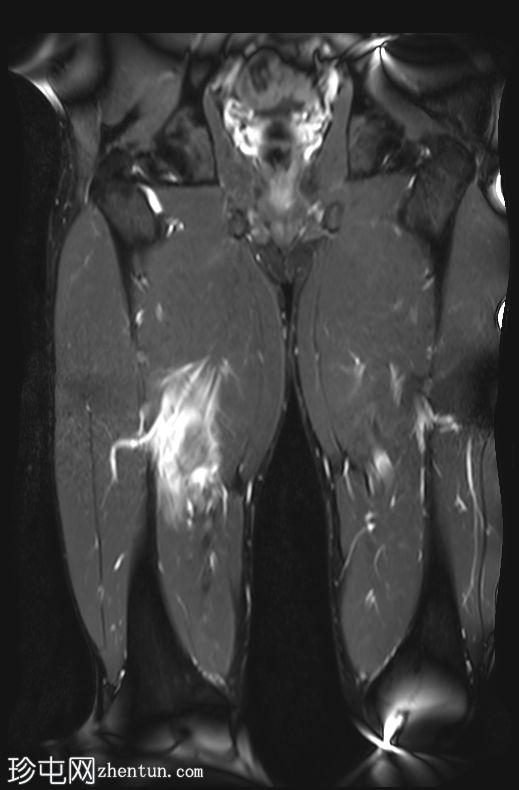

冠状位

T2加权像

内收长肌和内收短肌中远侧外侧可见羽状改变和肌内水肿,主要累及内收大肌,长15厘米,宽4厘米。未见明显血肿或完全性肌纤维撕裂。

后腱膜、邻近神经血管交界处及邻近肌间隙可见积液,少量积液向外侧扩散,沿肌间隙到达大腿中远侧。

内收肌腱完整,骨性附着点清晰可见,肌腱轻度增厚,中部可见腱周水肿;未见撕裂。

影像学特征符合英国田径肌肉损伤分级(BAMIC/BAC)2B级损伤,主要累及大收肌。未见明显的血肿或肌纤维完全撕裂。

后侧腱膜、邻近神经血管束及肌间隙可见积液,少量积液沿肌间隙向外侧延伸至大腿中远端。